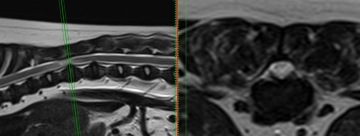

Veterinární chirurgové se učí od chirurgů lidských. Postupy aplikované na humánního pacienta se adaptují na pacienta zvířecího. Veterinární neurochirurgové umí odstranit nádor z mozku, operovat vyhřezlý meziobratlový disk, stabilizovat nestabilní páteř pomocí 3D tištěných operačních šablon.

Počítačové plánování stabilizační spinální chirurgie

Jedny z nejnáročnějších operací jsou zákroky na deformované páteři francouzských buldočků a mopsů. Vyžadují předchozí CT a MRI vyšetření, speciální 3D tištěné vrtací šablony pro bezpečné usazení implantátů a v zásadě vytvoření nové podpůrné páteře z polymetylakrylátu (kostní cement). Takové zákroky trvají i několik hodin a vyžadují extenzivní plánování a maximální soustředění celého operačního týmu během celého zákroku.